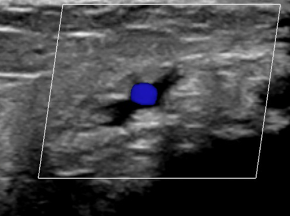

In performing an ultrasound scan, there was extensive soft tissue oedema; however, I was unable to find a musculoskeletal cause for her presentation. I then continued scanning the tarsal tunnel and up the leg where I located a deep vein thrombosis in the tibial vein.

I referred her to the Emergency Department at the local hospital. She was assessed and advised it was likely a musculoskeletal injury, as she lacked the typical risk factors for DVT. They planned to discharge her with a script for some anti-inflammatories. Given clinical ultrasound, her husband insisted on a formal ultrasound, which confirmed a DVT in the tibial vein.

It turned out she had a clotting disorder, Factor 5 Leiden.